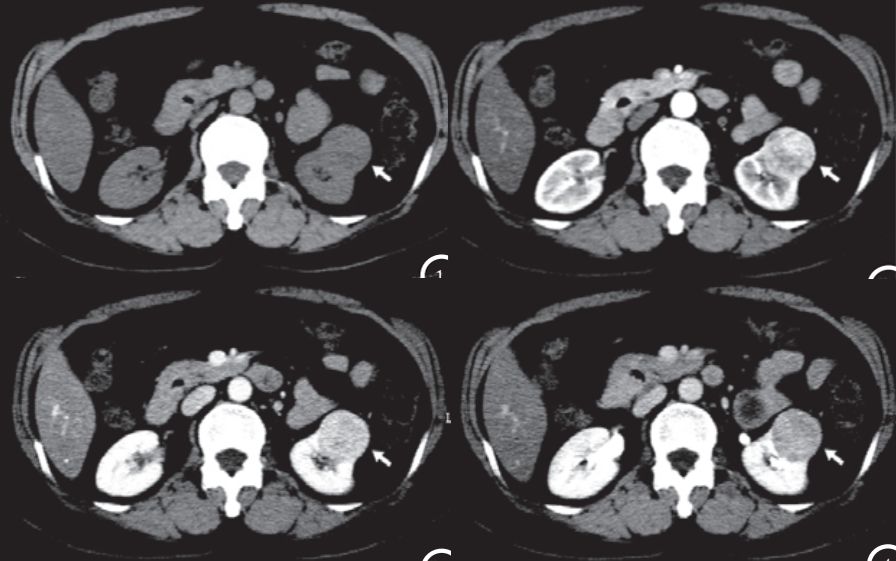

CASE 2 医学百科网 | YxBaike.Com

医学百科网 | YxBaike.Com

嗜酸细胞腺瘤。箭头所示「节段性强化逆转」